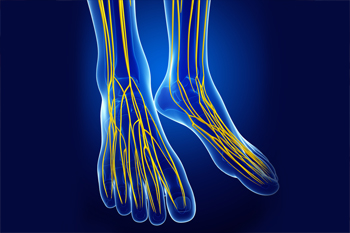

Charcot Marie Tooth Disease and the Feet

Charcot Marie Tooth (CMT) disease is a neurological condition characterized by a weakness and loss of sensation in the legs, hands, and feet due to nerve damage. This condition is genetic, affecting approximately 1 in every 2500 people. CMT develops gradually over time and progressively worsens. While there is no cure, a podiatrist can help you manage the symptoms of CMT in your feet. People with this condition may experience a change in the structure of their feet, developing high arches and hammertoes. Pain, muscle weakness, altered sensation, and muscle cramps are also common. Your podiatrist may recommend a treatment program consisting of foot strengthening and stretching exercises, orthotics, pain medication, and possibly surgery to reduce symptoms and maintain your mobility and quality of life. If you suffer from CMT disease, seeing a podiatrist can help.

Neuropathy

Neuropathy can be a potentially serious condition, especially if it is left undiagnosed. If you have any concerns that you may be experiencing nerve loss in your feet, consult with Ambrose Su, DPM from Cascade Foot Clinic. Our doctor will assess your condition and provide you with quality foot and ankle treatment for neuropathy.

What Is Neuropathy?

Neuropathy is a condition that leads to damage to the nerves in the body. Peripheral neuropathy, or neuropathy that affects your peripheral nervous system, usually occurs in the feet. Neuropathy can be triggered by a number of different causes. Such causes include diabetes, infections, cancers, disorders, and toxic substances.

Symptoms of Neuropathy Include:

- Numbness

- Sensation loss

- Prickling and tingling sensations

- Throbbing, freezing, burning pains

- Muscle weakness

Those with diabetes are at serious risk due to being unable to feel an ulcer on their feet. Diabetics usually also suffer from poor blood circulation. This can lead to the wound not healing, infections occurring, and the limb may have to be amputated.

Treatment

To treat neuropathy in the foot, podiatrists will first diagnose the cause of the neuropathy. Figuring out the underlying cause of the neuropathy will allow the podiatrist to prescribe the best treatment, whether it be caused by diabetes, toxic substance exposure, infection, etc. If the nerve has not died, then it’s possible that sensation may be able to return to the foot.

Pain medication may be issued for pain. Electrical nerve stimulation can be used to stimulate nerves. If the neuropathy is caused from pressure on the nerves, then surgery may be necessary.